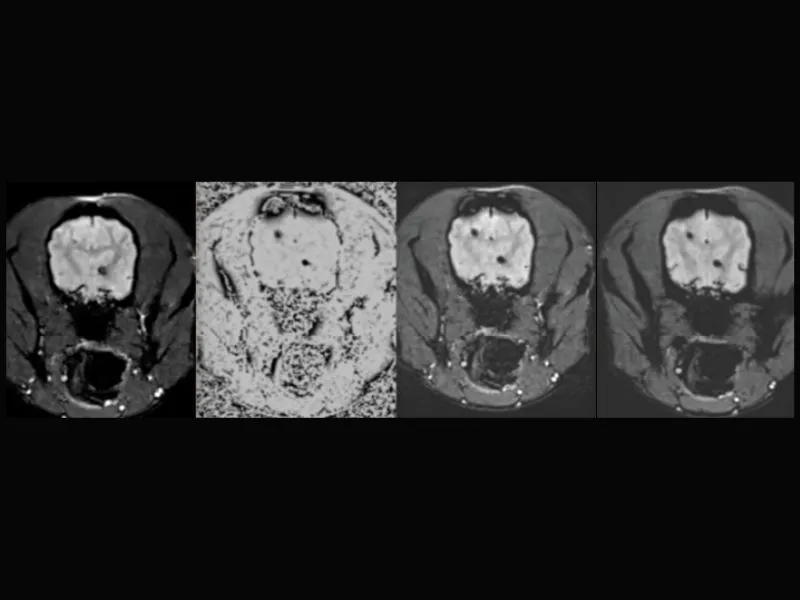

Clinical images

Small animals